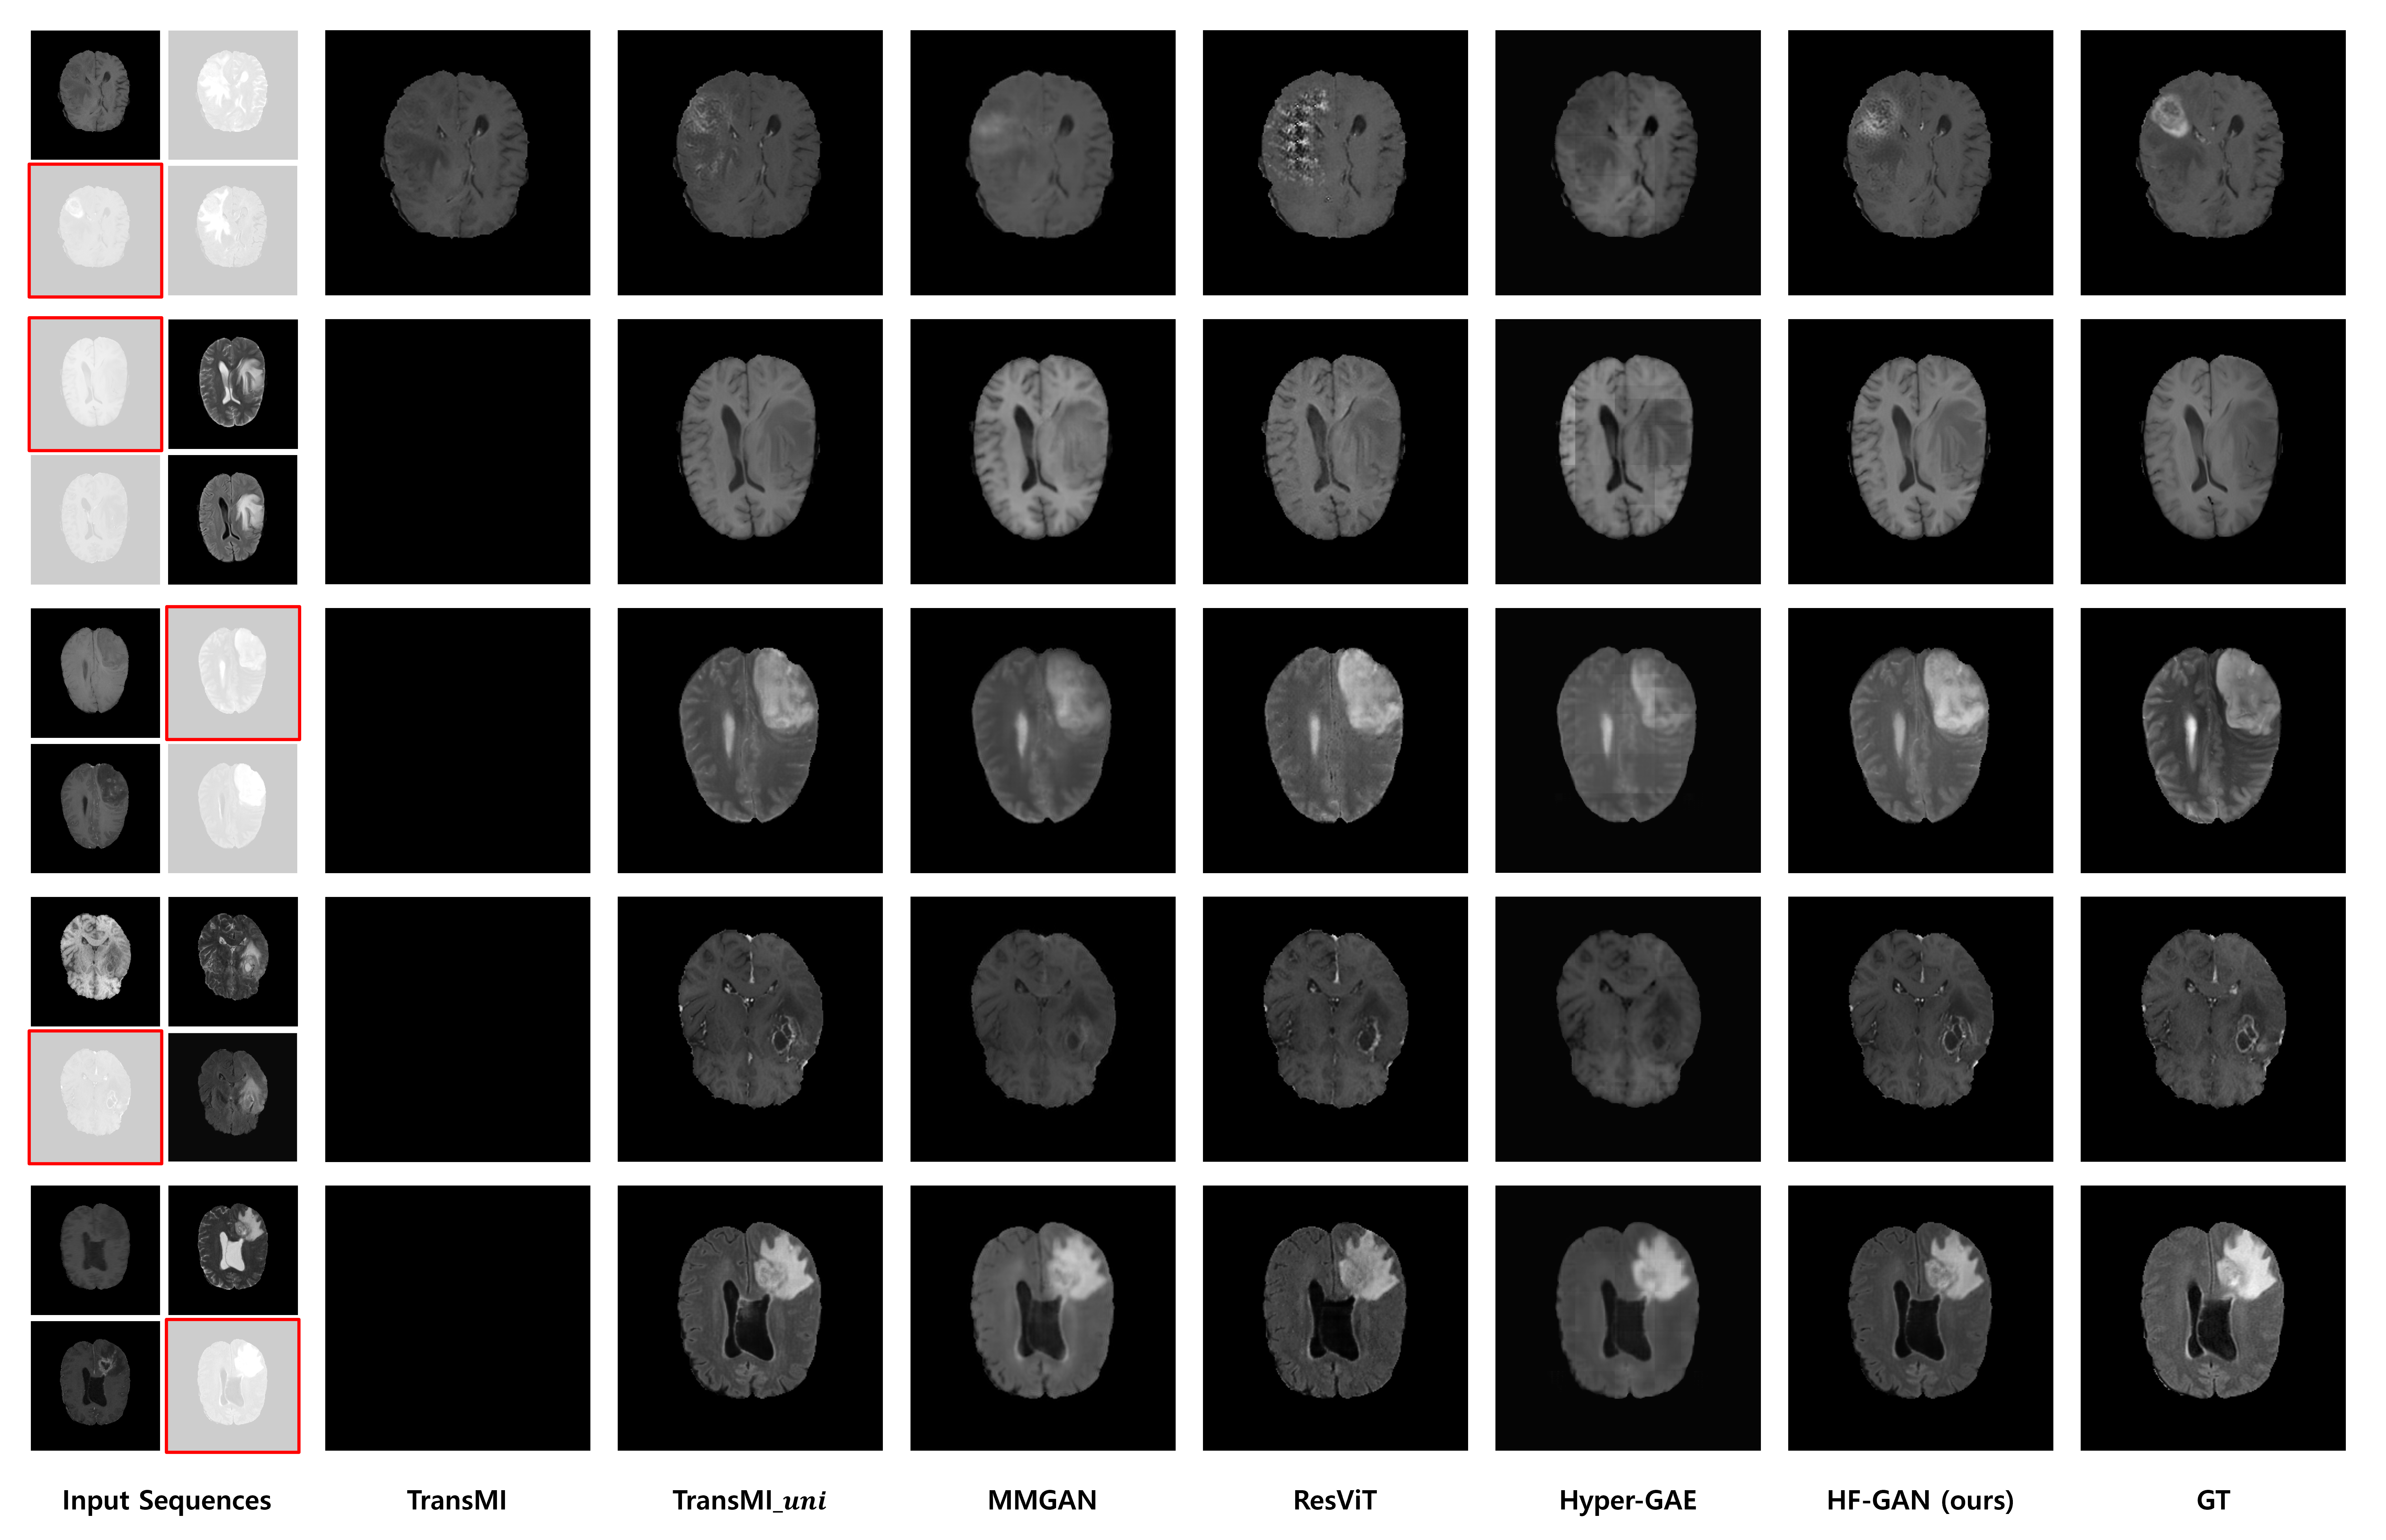

Refer to caption

Fig. 4: An example of synthesized results for the missing MR sequence on the BraTS dataset. The first column represents the input MR sequences: T1, T2, FL, and T1c are located from the top-left in a clockwise direction. The target MR sequence (GT) is highlighted by a red border.

The BraTS dataset is particularly challenging due to the high variability in tumor shape, size, and location, making it a robust testbed for a model’s ability to handle complex, clinically relevant scenarios. On this dataset, our proposed HF-GAN demonstrates a clear and statistically significant advantage. As detailed in Table 1, HF-GAN achieves the highest overall average PSNR of 30.27 and SSIM of 0.9393. This represents a notable improvement over the next-best performing methods, the 3D Hyper-GAE (PSNR 29.54, SSIM 0.9361) and our extended baseline TransMI (PSNR 29.45, SSIM 0.9305). This superior performance is a direct result of our hybrid-fusion architecture, which is constructed to extract and integrate the crucial complementary information that defines tumor boundaries and internal structures. This information is often challenging for single-pathway encoders to synthesize accurately. The qualitative results in Figure 4 provide compelling visual evidence of this advantage. As shown in the first row, ResViT faces challenges with the latent space. It struggles to synthesize tumor regions when the information provided is scarce, while it achieves great synthesis results when sufficient information is available. Hyper-GAE also yields a fuzzy and distorted image of the hyper-intense tumor. Conversely, HF-GAN offers a significantly clearer depiction of the pathology that aligns more closely with the actual ground truth. This demonstrates a remarkable capacity to deduce intricate pathological features, even with sparse source data.